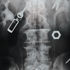

An innocent move by a five-year-old boy to buy a vuvuzela (plastic horn) almost ended tragically after the minor swallowed a loosely fitted cap on the device.

The minor is set to undergo a second surgery at the Kenyatta National Hospital (KNH) in a fresh attempt to remove the cap that is lodged in his lungs.

“He was operated on for close to eight hours, but the doctors were unsuccessful in removing the plastic cap. My son has been in and out of the Intensive Care Unit and the moments have been terrifying for me and my wife,” he explained.

“We initially thought that the cap would easily be flushed out or perhaps our son will undergo a minor surgery, but that has not been the case,” he revealed.

“He is scheduled to undergo the second surgery in the coming week. I am praying to God that, this time round, the doctors will succeed in removing the cap. I am keeping my fingers crossed,” Mr Kinaga said.